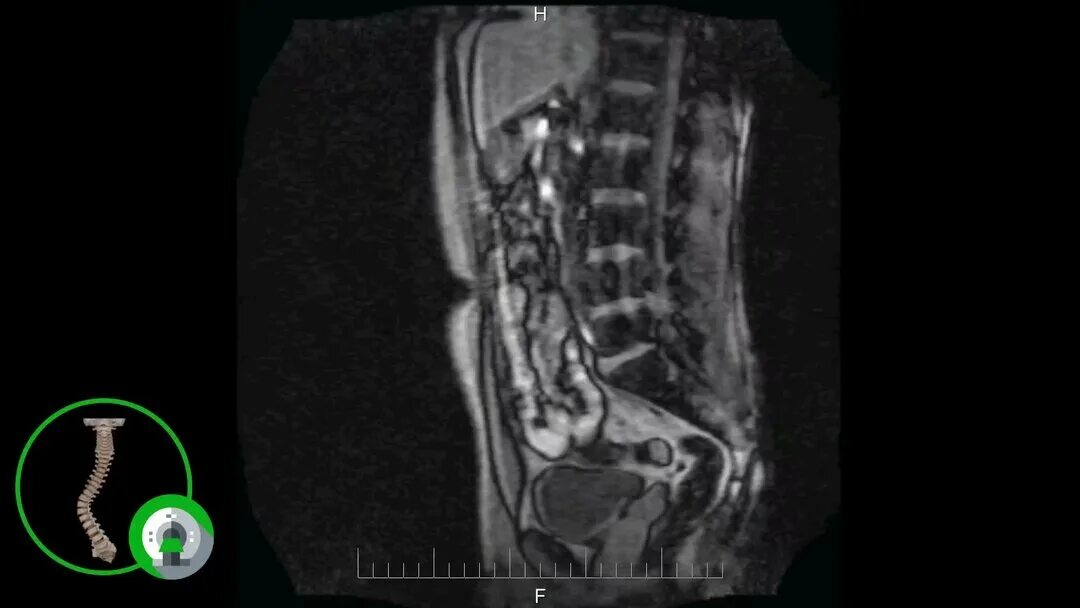

Мрт пояснично крестцового отдела тазобедренные суставы